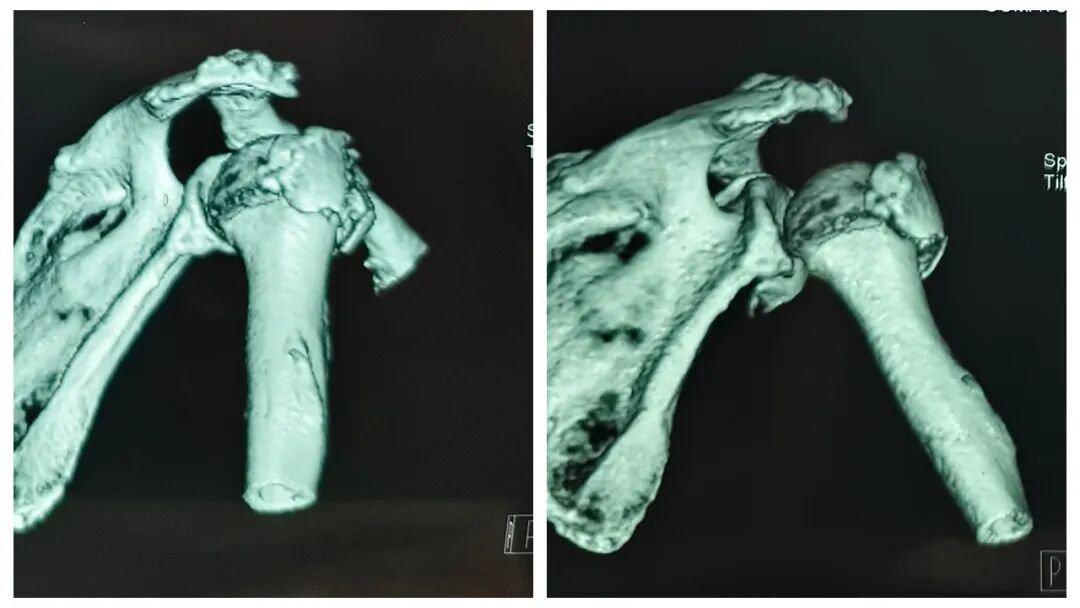

图片

图3  患者术中和术后情况

术中采用劈开三角肌的微创入路,结合辅助置钉装置,髓内主钉被精准送入肱骨近端。定制内植入近端金属骨小梁+微多孔结构的几何形状体,为肱骨头提供直接髓内支撑,有效复位并矫正肱骨头翻转嵌插,再由髓外接骨板向肱骨头内置入空心拉力钉和4枚定制锁钉,缝合周围肩袖韧带。全程保留骨膜,减少传统骨折手术的剥离复位等操作。手术在协和创伤骨科刘国辉主任和夏天教授团队的亲自操作下,仅用50分钟即完成骨折复位与固定,出血量极少。术后患者恢复良好。术后第二天刘国辉主任、夏天教授和吴发帅博士查房,患者恢复上臂大部分功能。